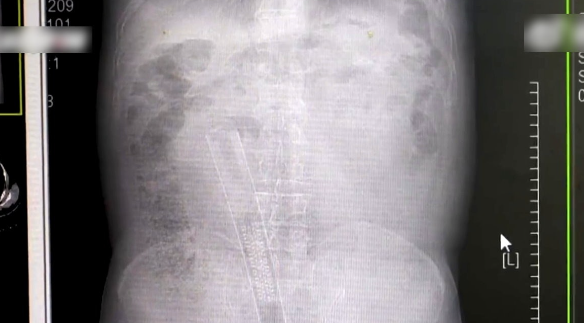

据《现代快报》报道,大爷6日上午被送到江苏常州的急诊,影像检查后发现塑料管已深入体内,末端甚至已经顶到肝脏附近,从解剖学看应该到了乙状结肠深处。

医疗团队通过内镜技术将塑料管取出,并将内镜送至结肠处观察,没有发现肠道穿孔,但是有黏膜水肿、溃疡形成。